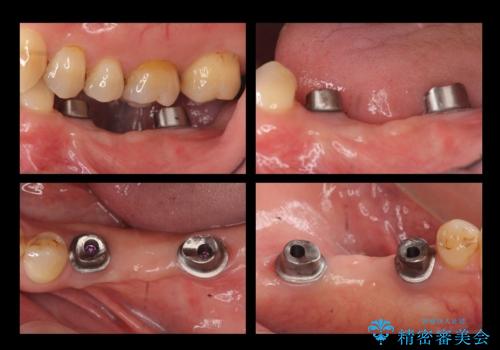

③インプラント埋入

④2か月待つ

⑤二次手術(APF)

⑥仮歯の装着

⑦最終的なセラミッククラウンの装着